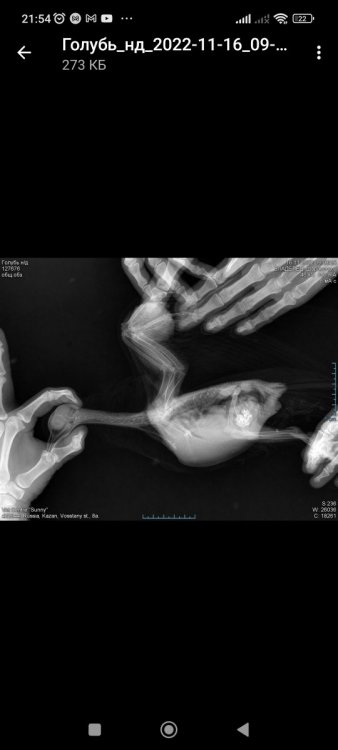

Zosia Опубликовано 21 ноября, 2022 #7 Опубликовано 21 ноября, 2022 нарост (по виду старый абсцесс, зафибриненный)- омывать смесью №2, и внутри тоже. Пероо у основания все состричь, контролировать "ножку". На рентгене все кости перавого крыла сохранены, правда немного рыхло выглядят ,но возможно такой ракурс, крыло чуть повернуто. 3